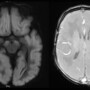

A term, appropriate-for-gestational-age neonate with normal APGAR scores and no history of perinatal hypoxia presented with seizures on day 2 of life. There were no antenatal or perinatal complications. Initial consideration was hypoxic–ischemic encephalopathy (HIE); however, the clinical history was discordant with this diagnosis.

DWI: Diffuse, symmetric cortical thickening with widespread diffusion restriction, involving bilateral cortical and subcortical regions, basal ganglia, thalami, and cerebral peduncles.

SWI: Susceptibility-weighted imaging shows no hemorrhage

Diagnosis: Targeted metabolic evaluation followed by genetic testing confirmed molybdenum cofactor deficiency.